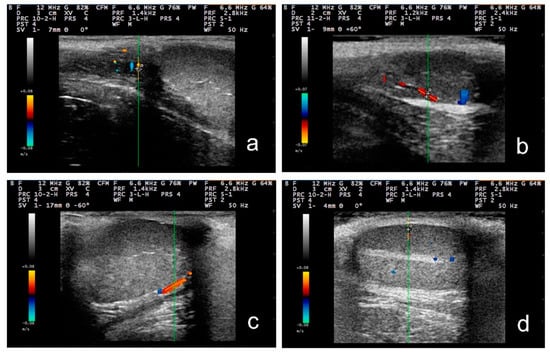

3.2. B-Mode Examination

3.3. Pulsed-Wave Doppler

4.2. Differences in the Findings between the Regions of the Testis

4.4. Proposed Segments of the Artery and Haemodynamic Parameters for Doppler Evaluation